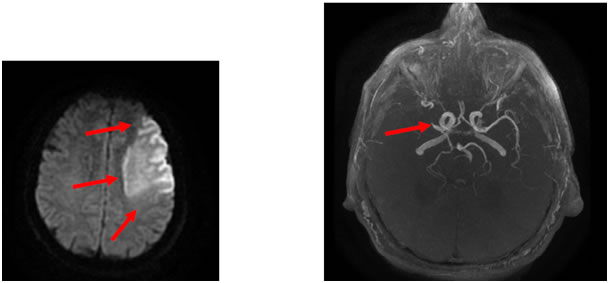

La Neurologie Vasculaire ou Neurovasculaire est la partie de la neurologie spécifiquement dédiée à la prise en charge des AVC ou attaques cérébrales.

L’individualisation du Neurovasculaire au sein de la Neurologie se justifie par:

• la fréquence des AVC, responsables de 40 à 50% des hospitalisations en Neurologie

• la nécessité d’une unité très spécialisée de prise en charge, que l’on appelle Unité Neuro-vasculaire (ou UNV), regroupant médecins et personnel paramédical habitués à prendre en charge les malades en extrême urgence. Initialement, les patients sont accueillis dans des lits de soins intensifs, permettant une surveillance très étroite des fonctions vitales et de l’état neurologique.

Cinque Terre Cinque Terre

Au sein d’une UNV, trois priorités sont menées de front :

• débuter au plus vite les médicaments pour limiter les conséquences de l’attaque cérébrale et éviter sa récidive. Lorsque les personnes arrivent dans les toutes premières heures, une thrombolyse (perfusion d’un médicament pour dissoudre le caillot) peut être proposée

• réaliser les examens permettant de comprendre la cause de l’attaque et d’évaluer son pronostic

• débuter la rééducation dés les premiers jours pour stimuler la récupération

A l’issue de la phase aiguë, l’UNV organise la suite de la prise en charge du patient (retour à domicile, départ en service de soins de suite ou centre de rééducation, etc…). Une attention particulière est également portée à la prévention, car il faut éviter la survenue de récidives et d’autres troubles vasculaires sévères tels qu’un infarctus du myocarde